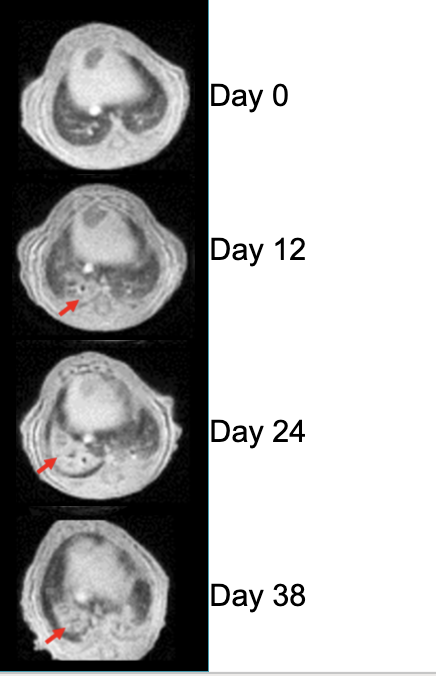

MRI of lung in mice

UTE of Disease Progression in Transgenic Mice w/ Lung Fibrosis​